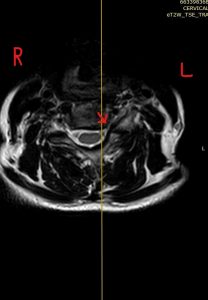

Ο απεικονιστικός έλεγχος με μαγνητική και αξονική τομογραφία της σπονδυλικής στήλης ανέδειξε εικόνα δισκοκήλης στα επίπεδα Α5/6 και λιγότερο Α4/5. Το σημαντικότερο εύρημα ήταν η πλάγια τρηματική στένωση με πίεση επί των ριζών Α6 & Α5 αριστερά.

Διενεργήθηκε πρόσθια δισκεκτομή και αποσυμπίεση των ριζών στα επίπεδα Α4/5 & Α5/6